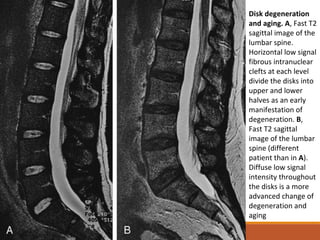

Disk degeneration

and aging. A, Fast T2

sagittal image of the

lumbar spine.

Horizontal low signal

fibrous intranuclear

clefts at each level

divide the disks into

upper and lower

halves as an early

manifestation of

degeneration. B,

Fast T2 sagittal

image of the lumbar

spine (different

patient than in A).

Diffuse low signal

intensity throughout

the disks is a more

advanced change of

degeneration and

aging